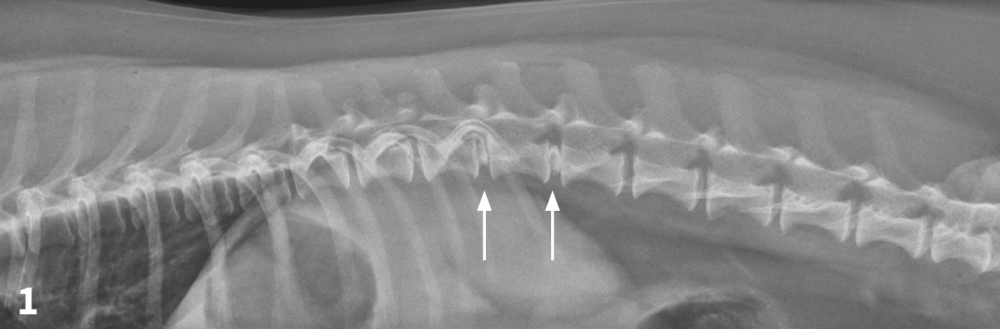

Product code: Degenerative disc disease discount in dogs

Degenerative disc disease discount in dogs